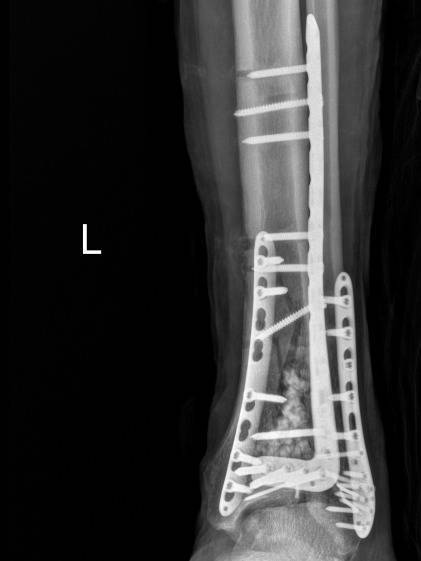

r3月20日,急诊外科团队实施了左胫腓骨远端骨折切开复位内固定术,成功复位骨折、稳固固定,恢复左下肢正常力线。

▲骨折终极固定术后复查影像。